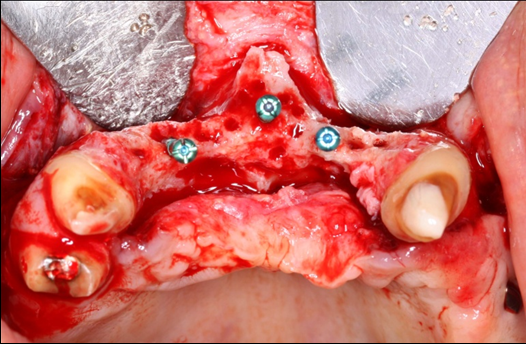

The surgical procedure was done under intravenous sedation using Fentanyl and Versed. Local anesthetic was used and a supra-crestal horizontal incision made on the palatal aspect of the anterior maxilla. A mucoperiosteal flaps were elevated, exposing a severely resorbed ridge of the pre-maxilla (Figure 2). Decortication was conducted with a round carbide bur in order to perforated the cortical aspect of the bone and expose the cancellous bone, to increase vascularity to the recipient site. Three screws were fixed parallel to the adjacent teeth, serving as “tent pole”. The screws had 14 mm length and approximately 6-8 mm of the tenting screws were exposed to the oral cavity (Figure 3). An absorbable collagen sponge (ACS) carrier/matrix was embedded with 12 mg of rhBMP-2 at 1.5 mg/mL (Infuse® Medtronic Sofamor Danek, Memphis, TN, USA) and allowed to absorb for approximately 20 min. The rhBMP-2/ACS was cut into strips, half of the strips were added to the natural bone mineral component derived from bovine bone (Geistlich Bio-Oss® granules small - 0.25 to 1 mm, Geistlich Pharma, Germany). Initially, some strips of rhBMP-2/ACS were placed over the buccal aspect of the residual alveolar ridge of the pre-maxilla, followed by strips mixed with bovine bone (Figure 4). The three screws were fully covered by rhBMP-2/ACS strips. Finally, a titanium mesh was adapted over the entire rhBMP-2/ACS graft and fixed with 2 monocortical screws, one on the buccal aspect and one on the palatal aspect of the ridge, respecting a 2 mm distance from the mesh to the adjacent teeth (Figure 5). Extensive undermining incision was conducted on the apical aspect of the buccal flap in order to achieve primary closure.

Figure 2.Occlusal view of the pre-maxilla after elevation of amucoperiosteal flap. Noteright and left pre-maxilla buccal plate concavities due to severely resorbed ridge. The central tenting screw is located mid-way into the nasal spine.

Figure 3.Frontal view of the pre-maxilla after elevation of amucoperiosteal flap. Note 6-8 mm of the tenting screws length are exposed.